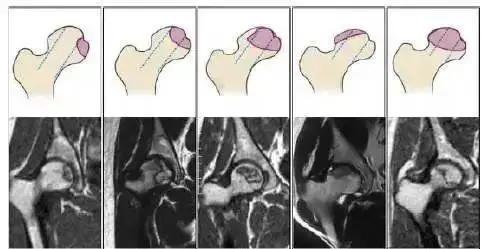

股骨头坏死是不是无法根治?股骨头坏死为什么一直治疗不好?股骨头坏死如何治疗好?

网上有关股骨头坏死的问题被网友频繁搜索,有关于股骨头坏死的治疗,每个患者的病情不一样,治疗方法也不同,但是,治疗后股骨头的恢复却是有共同的原则的,今天我们就一起来了解下股骨头坏死必经的恢复阶段。